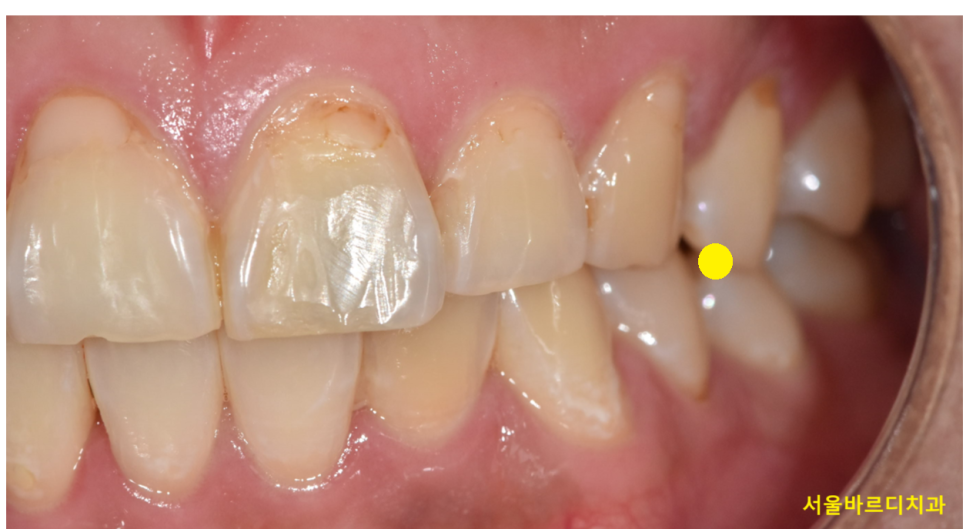

충치가 있어도 안아픈 경우가 대부분입니다.

특히 얕은 충치의 경우에는 검사 시 발견되는 것이 대부분입니다.

아파서 치과를 방문할 경우

이미 충치가 신경까지 근접하여 아프기 때문이죠~

250429 치아의 2/3 이상 충치가 침범하였을 때 통증을 느끼는 경우가 많습니다 .

증상이 상당히 진행된 상태에서 내원한 것으로

안아팠을 때

충치의 크기가 작을 때 치료받는 것이 현명합니다.